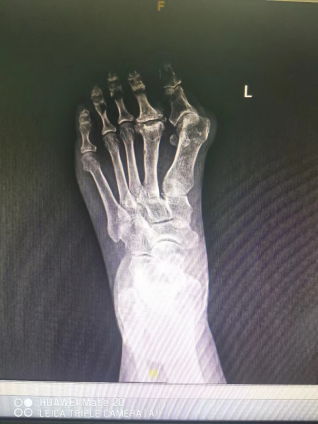

关节成形术